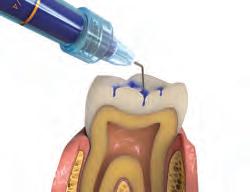

Sable Seek caries indicator contains FD&C dyes, and Seek caries indicator contains D&C dyes in a glycol base. Both are used to stain carious and demineralized dentin.

Seek and Sable Seek caries indicators stain carious and demineralized dentin and can be very useful for difficult-to-see areas, for example; undercuts of preparations, dark dentin, areas along the DE junction, etc. Green Sable Seek caries indicator helps visualization of decay in deep caries cases to help avoid pulp exposures.

PROCEDURE

dentin) with slow-speed round bur or excavator. To control overexcavating near the pulp, remove final portion of caries with hand excavator.